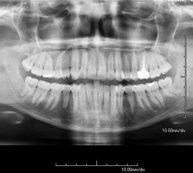

- Mandibular X-ray

This technique uses X-ray rendered imaging for examining the jaw. Indicated for: trauma, congenital anomalies.